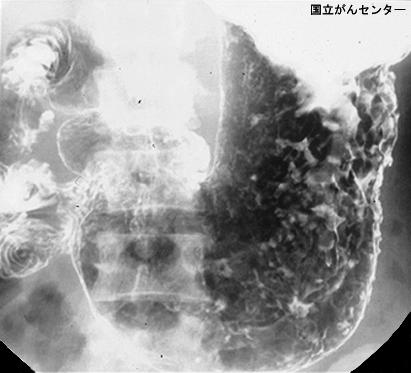

clasificación del pacienteTumor de tipo Metastásico/

parte(separada por órganos)estómago(región)/mas de dos

método de exámenRayos X

clasificación ectoscópica de tumoresTipo 4(Tipo difusamente infiltrado)/

diámetro mayor del tumor40 -

grado de penetracións(a)

múltiples tumores(en un mismo órgano)ausente

múltiples tumores(en varios órganos)presente(metacrónico)